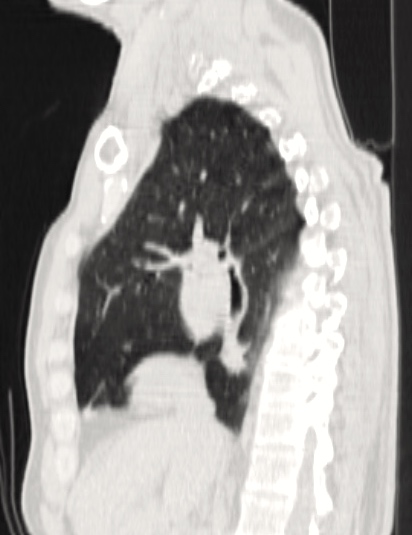

This video presents the case of a 71-year-old male patient, who was diagnosed with a centrally located left lung tumor. Endobronchial ultrasound-guided needle aspiration confirmed an adenocarcinoma. PET-CT revealed no lymph node or distant metastasis. After the chest CT, the authors determined that a pneumonectomy was the only option for surgical resection (Figure 1). Spirometry was suboptimal (FEV1: 58%), but VO2-max was normal (20.4 mL/kg/min). A single incision VATS (SIVATS) approach was used for a left pneumonectomy and lymph node dissection in this patient.

| Figure 1A: Lateral CT scan. | Figure 1B: CT scan. |